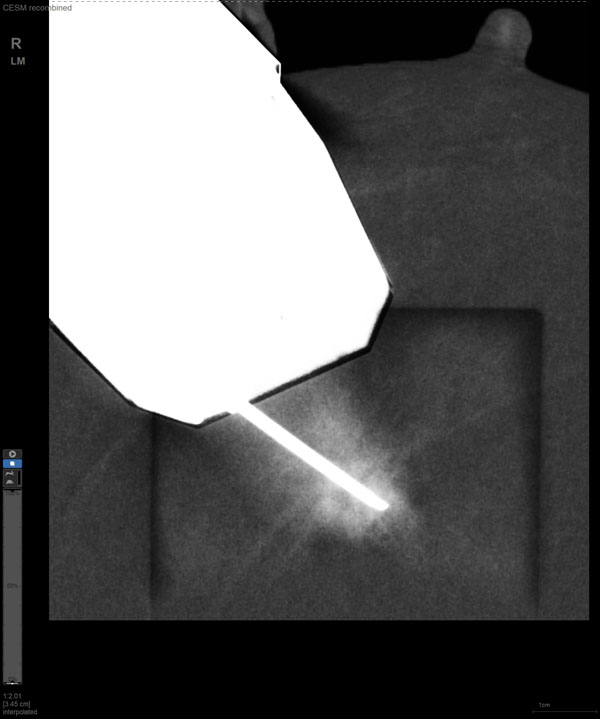

CEM引導下穿刺

某患者增強磁共振成像MRI顯示腫瘤周邊有活性,中心區域有組織壞死。為得到準確的病理結果,穿刺靶區需避開腫物壞死區域。在與患者主管醫生充分討論后,放射科醫生為患者行CEM引導下穿刺活檢術。術中,CEM檢查腫物同樣顯示為環形強化,巧妙避開壞死區域后,穿刺靶區選擇了腫物增強早期明顯強化區域,術程順利,僅用時15分鐘。術后該患者病理結果為浸潤性導管癌Ⅱ級。